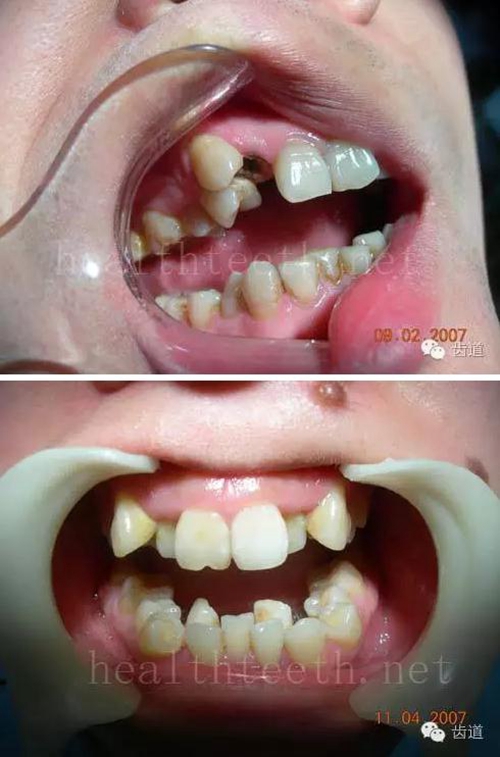

17.jpg

青少年牙周炎,20多歲牙齒破壞到這個(gè)程度